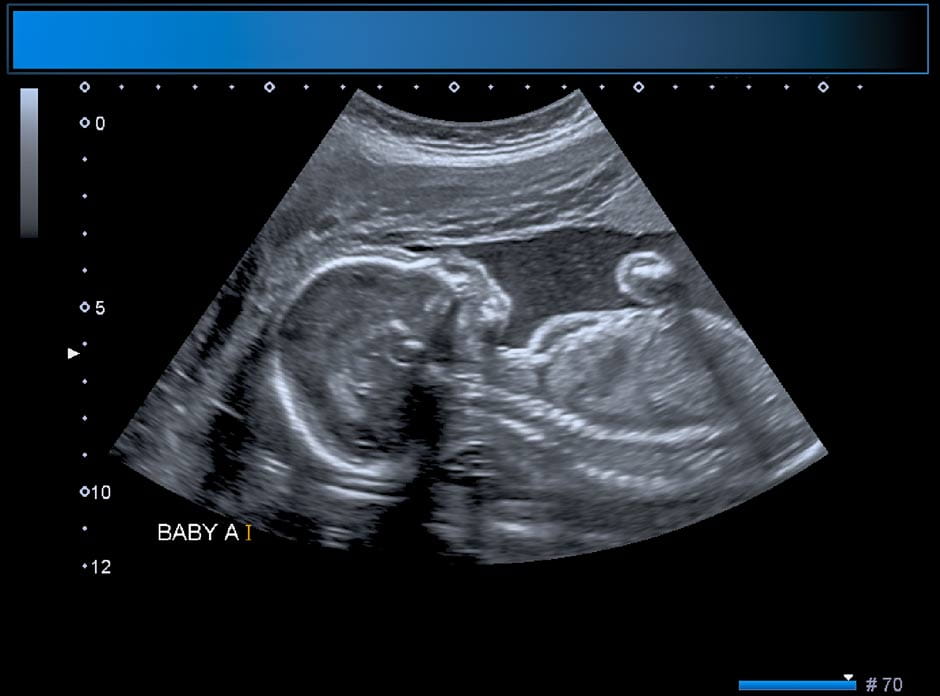

Here’s what an early pregnancy might look like on an ultrasound:

- Between eight and 12 weeks: The first official ultrasound is usually performed at this time. This early scan confirms the pregnancy, estimates your due date, checks for the baby’s heartbeat and determines whether you’re carrying one baby or multiples.

- Check if you’re carrying more than one baby

This ultrasound typically lets you see your baby’s face, hands, movements and biological sex for the first time. It’s important to remember that this is a diagnostic procedure, and our priority is to obtain diagnostic images to help our physicians determine the health of your baby. You’re not permitted to record during the ultrasound examination, and we’ll send you a link to electronically view your images after the exam is complete. We can’t guarantee that you will see the baby’s face, nor do we routinely provide 3D or 4D images. Again, our focus is on the baby’s health.

Video screens are positioned in the ultrasound room so that you’ll be able to view the images as the test is happening. After the ultrasound, you will be sent digital images of your baby.